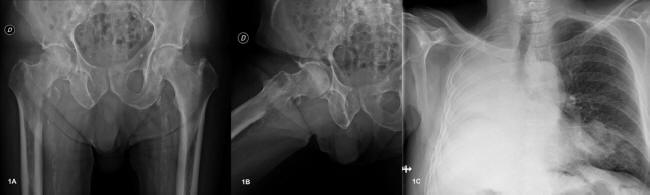

There is an avulsion fracture involving greater trochanter of right femur. An avulsion fracture is a bone fracture which occurs when a fragment of bone tears away from the main mass of bone as a result of physical trauma.

Therefore, correct planning of the radiographic examination should be considered to prevent possible mistakes. In young patients, they are typically an avulsion fracture caused by forceful contraction of the gluteus medius and minimus in the case of the greater trochanter and the iliopsoas in the case of the lesser. Thus, a fracture of the greater trochanter could cause avulsion injury of these. Greater and lesser trochanter fractures are rare and have good prognosis. Stresses due to obesity have been implicated. They may be divided into those involving epiphyseal separation of adolescence and true fractures of we are aware of only two case reports of avulsion fracture of the greater trochanter following trauma in adolescents.4,5 the patients were aged twelve. The gluteus medius and gluteus minimus are abducent muscle groups with attachments located on the greater trochanter. No callus formation? answered by dr. The avulsion of the apophysis of the greater trochanter is rarely described in literature, even as an example of greater trochanter fracture. There is an avulsion fracture involving greater trochanter of right femur. Most often, this occurs during sudden movements and changes in direction. It has at etiological factors indirect mechanisms (avulsion) and direct mechanisms. Rarely involve the greater trochanter (1, 11), presumably. Because of the high mechanical forces which. Fractures of the greater trochanter usually heal in 4 to 6 weeks. It tends to occur as a consequence of a. The apophyseal fracture or avulsion of the greater trochanter occurs in skeletally immature patients.